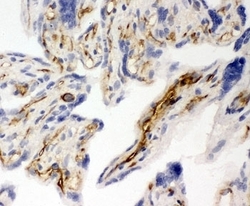

- Submitted by

- NSJ Bioreagents (provider)

- Main image

- Experimental details

- IHC-F testing of CD31 antibody and human placenta tissue